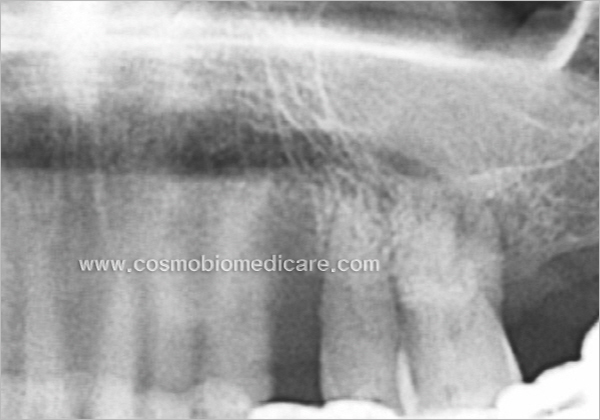

• Case1

• Case2

• Case3

• Case4

• Case5

• Case6

• Case7

• Case8

• Case9

• Case10